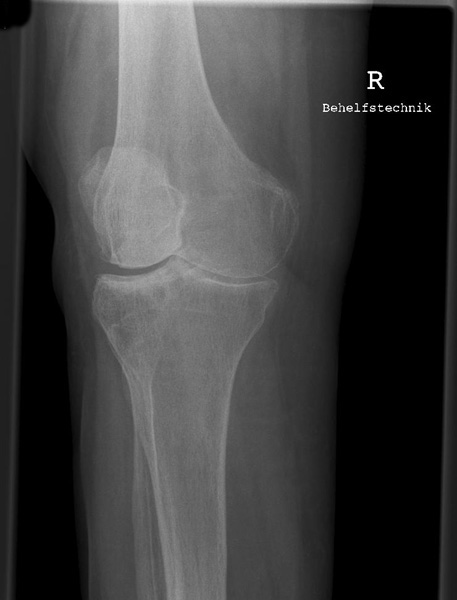

Knie seitlich

126_3.jpg

Fehler

Die Femurkondylen stehen nicht senkrecht übereinander. Zudem wird die Patella vom lateralen Anteil der Femur und das Fibularköpfchen vom Tibiakopf überdeckt.

Abhilfe

Abhilfe bringt eine weitere Drehung des Patienten nach vorne in Richtung Patella, damit die Kondylen wieder übereinander liegen.